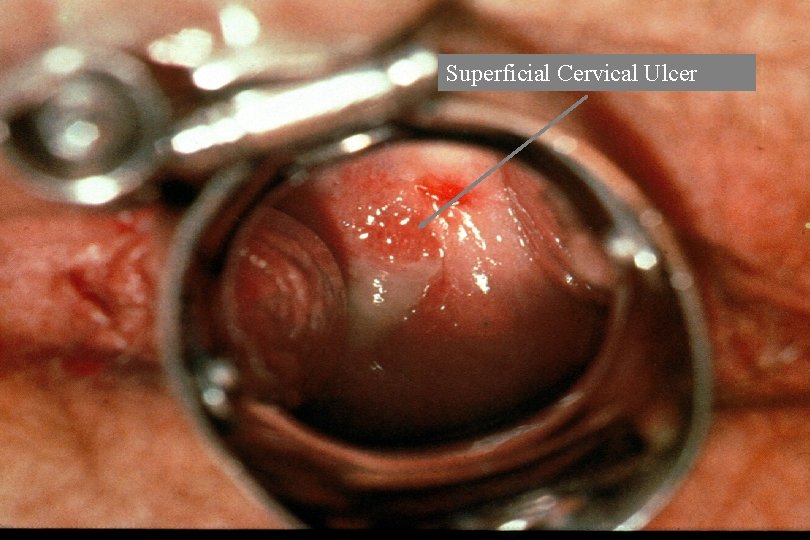

Superficial Cervical Ulcer

Diagnosis of Cervicitis · · Signs: specific, but insensitive. Include: - easily induced bleeding (“friability”) “Endocervicitis” - mucopurulent discharge: swab test - edematous ectopy - discrete lesions (ulcers): can occur anywhere Increased PMN (“polys; ” >10 -30/HPF) on Gram stain of endocervical secretions: may be sensitive for endocervicitis, but not specific; variable in ectocervicitis

STD as a Cause of Cervicitis · · · Endocervicitis (mucopurulent cervicitis, MPC) - Gonorrhea Chlamydia ? Mycoplasma genitalium Other/unknown Ectocervicitis: often associated with vaginal infection - Trichomoniasis Candida albicans (probable but infrequent) Bacterial vaginosis (? ) Discrete lesions - Herpes simplex virus (and other ulcerative agents) Syphilis Human papillomavirus Cervical cancer